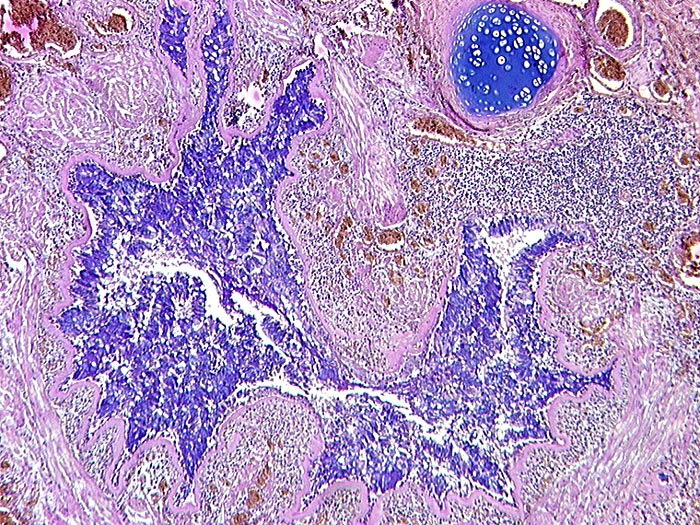

AP/ Asthma bronchiale

Asthma bronchiale

Bronchus

Morphologie

Pathologischer Befund